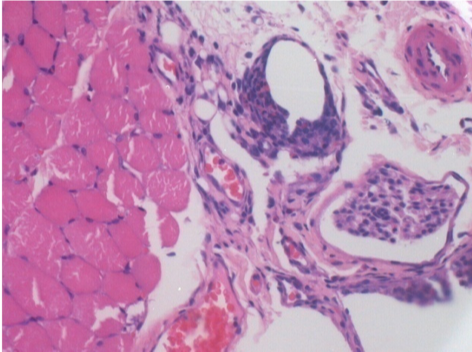

7 months (D210)after Endopeel IM Injection 0.1ml in the right pretibial muscle.

Complete Restitutio ad integrum after 7 months